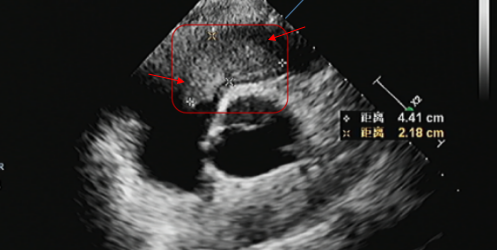

去年 8 月,李先生又感到胸闷及活动后气短,检查发现在右心室流出道又有新发粘液瘤,随后去外院就诊,进行了基因检测,提示为卡尼综合征(Carney 综合征)。近期自觉症状加重,超声检查显示肿瘤明显增大,堵塞右心室流出道血流,还有明显的三尖瓣关闭不全。为寻求进一步治疗,李先生慕名来到西安高新医院心脏大血管外科。